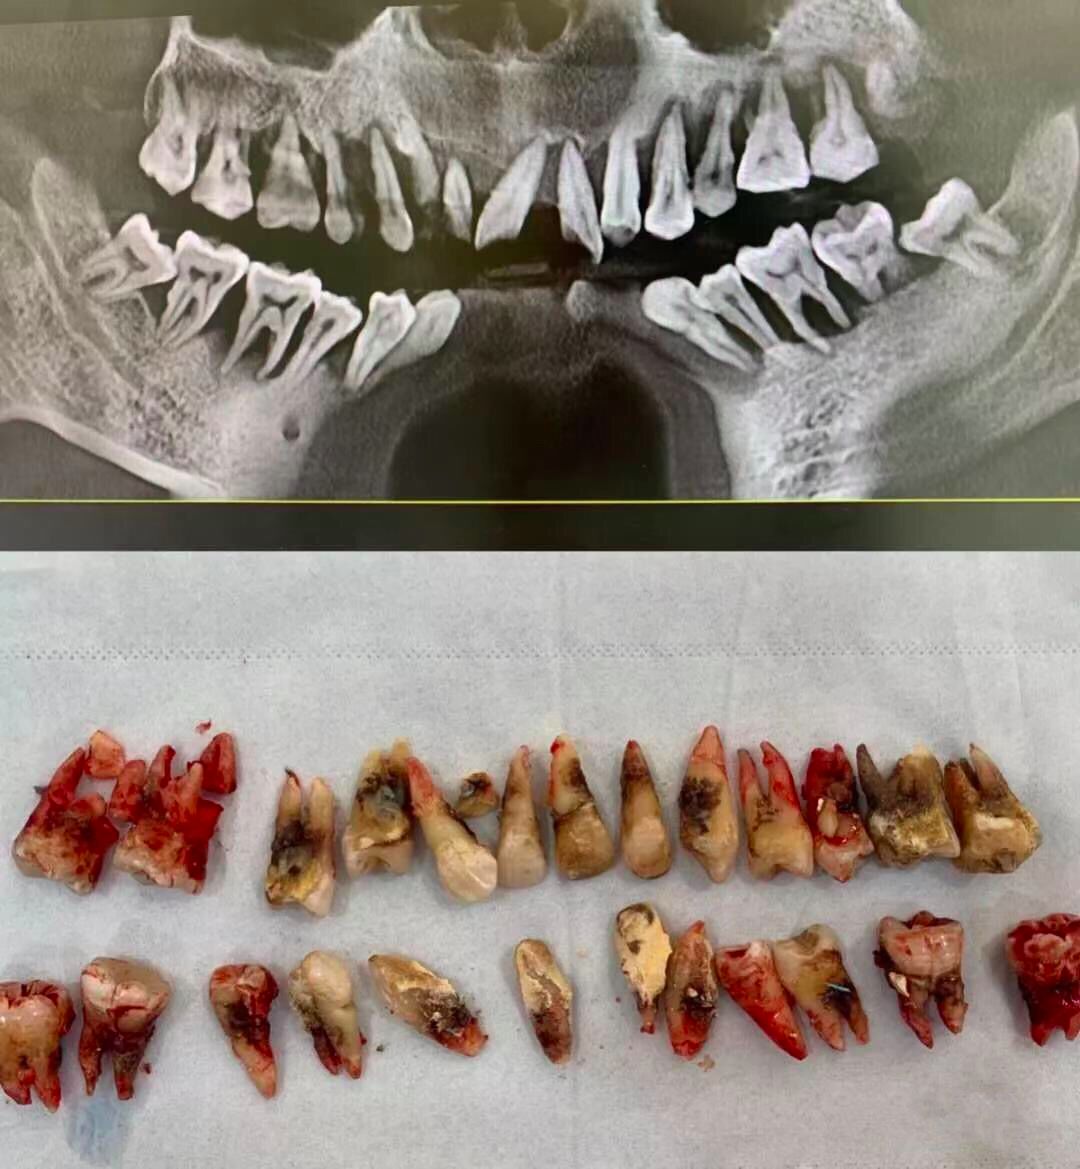

这是一个 30 多岁的小伙子,只是因为「牙齿松动」来就诊。

但等待他的,却是晚期牙周炎患者的最终归宿——全口牙松动,拔除。

@西安牙医老聂 供图

换句话说,他看起来一颗牙也不缺,但其实一颗牙也没有了——这就是晚期牙周炎患者面对的「无牙窘境」。